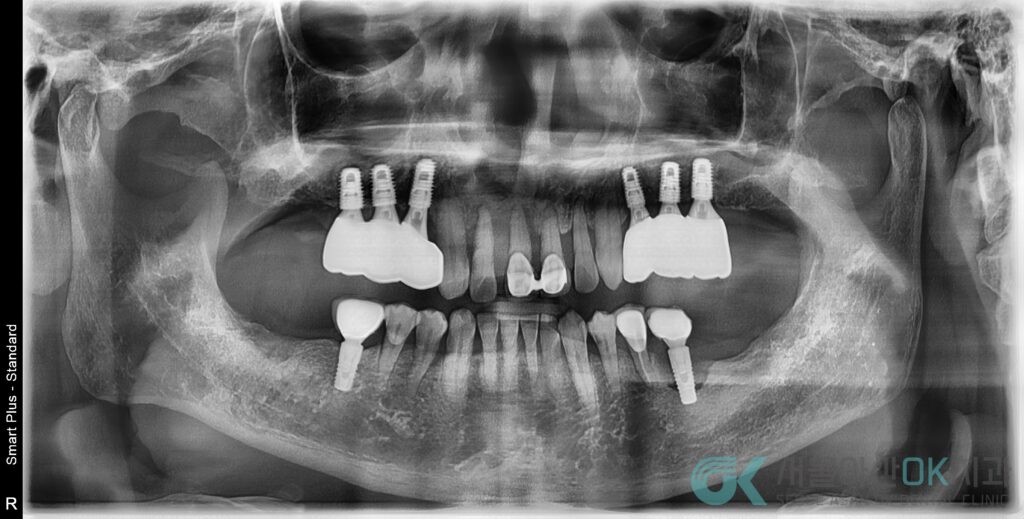

치과를 방문하신 이 환자분 께서는 파노라마 X-ray 촬영으로 전체 뼈 상태 및 기존 보철 상태를 확인하고 구내 사진으로 앞니 배열, 잇몸 라인, 미소선 등을 기록하였는데요.

그 결과 K05.31 만성 복합치주염으로 전악적으로 잇몸뼈가 많이 내려간 상태라는 것을 파악할 수 있었습니다.

특히 #36 부위는 수직 골 소실이 뚜렷하게 관찰되었으며 이외에도 여러 부위에서 4–5mm 이상의 치주낭, 치은연하 치석, 부종, 출혈이 반복적으로 보이는 양상을 확인할 수 있었습니다.

- 타 치과에서 치료한 #46 임플란트

- “흔들리는 것 같다”는 느낌

- X-ray 상 보철물 경계 불량, 나중엔 스크류 파절까지 동반